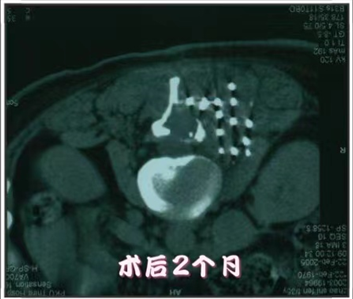

放射性粒子植入术

放射性粒子治疗是利用现代影像学技术将具有放射性核素直接插到肿瘤靶体积内或肿瘤周围,通过放射性核素持续释放射线对肿瘤细胞进行杀伤。